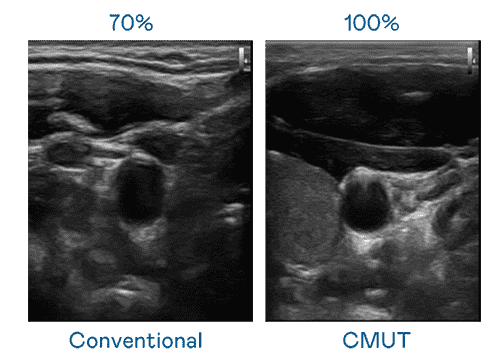

CMUT 技术是一种用电容式微机电元件来产生超音波讯号的技术。。与传统 PZT 压电式技术相比,,,,CMUT 频宽增加 30%,,,更宽频的超音波讯号让影像解析度大幅提升,,,,是实现高影像品质医疗超音波扫描、、促进精准医疗发展的关键技术。。。

大频宽带来超清晰影像

超音波影像的解析度高低,,,首先取决于探头能发出的讯号频宽。。。。z6mg·人生就是博 CMUT 可提供高清晰的超音波讯号,,提供高频宽、、、高灵敏度、、、影像纹理细节更高的超音波影像,,协助医护人员缩短影像判读时间及利用精准的医疗影像进行诊断。。。